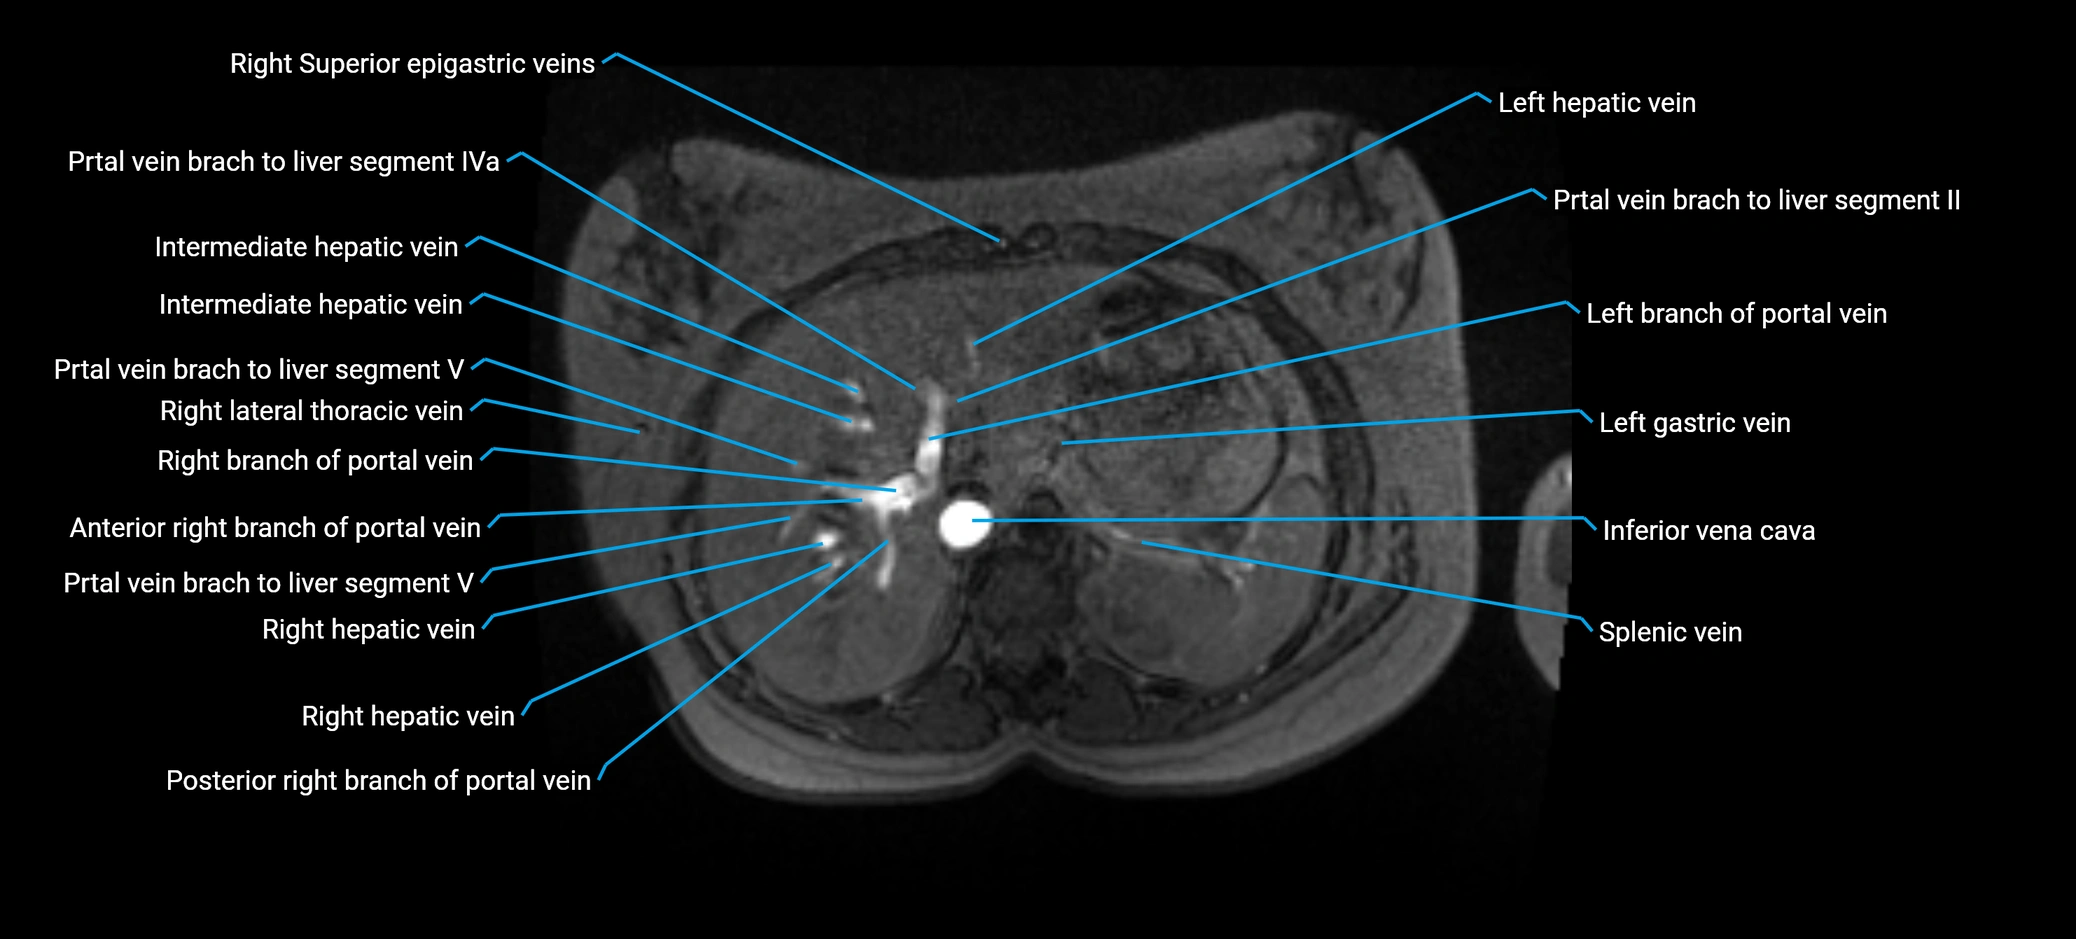

Anterior right branch of portal vein

The anterior right branch of the portal vein is a major intrahepatic division of the right portal vein. After the main portal vein bifurcates into right and left branches, the right portal vein divides into anterior and posterior segmental branches.

The anterior right branch supplies the anterolateral liver segments (Segment V) and anteromedial liver segments (Segment VIII) within the right hepatic lobe. It operates as a key vascular route delivering nutrient-rich portal venous blood to the central and superior right liver.

This segmental vasculature is of major importance in hepatic surgery, embolization, segmental resection, transplantation, and imaging-based liver segmentation.

MRV TOF (Time-of-Flight MR Venography):

• Appears as a bright, high-signal vascular channel representing flowing blood

• Clearly shows branching pattern of right portal vein into anterior and posterior branches

• Best in coronal or axial reconstructions for segmental mapping

• No need for contrast, relies on flow-related enhancement

MRI image

image